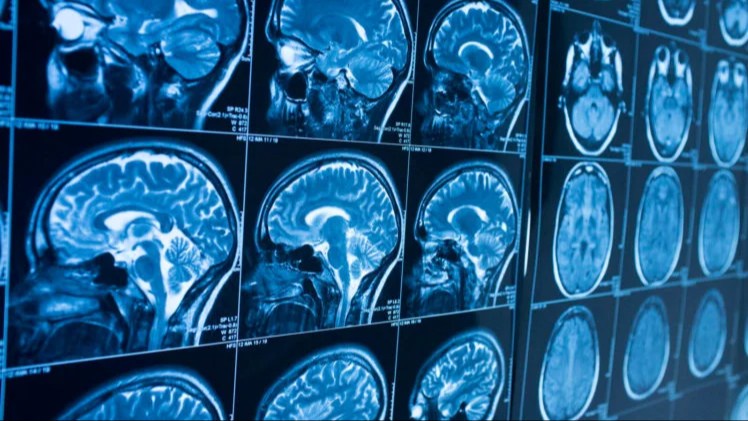

Fibronektin 1 (FN1) genining himoya varianti amiloidning toksik shakllarini gematoensefaliya to'sig'i orqali miyani tark etishiga imkon beradi. Amiloidning paydo bo'lishi Alsgeymer kasalligining boshlanishini ko'rsatadi, ammo kasallikning belgilari miyada ularning to'planib qolishi tufayli o'zini namoyon etadi.

Fibronektin gematoentsefaliya to'sig'ining tarkibiy qismi bo'lib, miya qon tomirlarini o'rab turgan va miya ichidagi va tashqaridagi moddalarning harakatini nazorat qiluvchi membranadir. Odatda u juda oz miqdorda mavjud, ammo Alsgeymer kasalligi bilan og'rigan odamlarda uning ishlab chiqarilishi ortadi. Fibronektinni kodlovchi genning yangi varianti ushbu komponentning ortiqcha to'planishini oldini oladi.

Tajribalar hayvonlarda fibronektinni kamaytirish amiloid klirensini oshirib, Alsgeymer kasalligidan kelib chiqadigan boshqa zararlarni kamaytirishini ko'rsatdi, deb xabar beradi lenta.ru.

Olimlarning ta'kidlashicha, olingan natijalar fibronektinga asoslanagn davolash usuli odamlarda kasallikning rivojlanishini to'xtatishi mumkinligini ko'rsatmoqda.